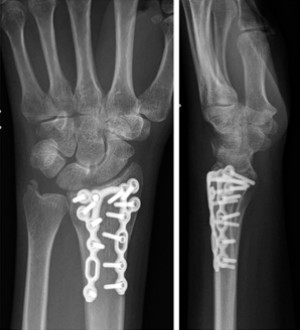

Случай ②